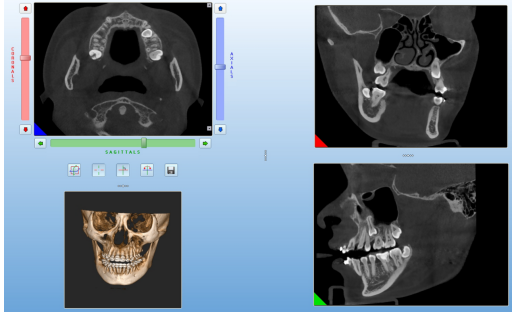

3、锥形束CT(CBCT):具有扫描速度快、空间分辨率高、辐射剂量小、图像伪影少等优点,作为牙科影像新的影像学检查手段,在口腔临床得到越来越广泛的应用,其应用范围涉及口腔正畸学、牙体牙髓病学、牙周病学、种植医学、口腔颌面外科学等。CBCT是口腔三维成像技术的一次飞跃,其对牙颌面牙齿、骨骼的良好成像效果,高质量的三维立体图像,有助于临床作出精确诊断、治疗计划的制订与实施。